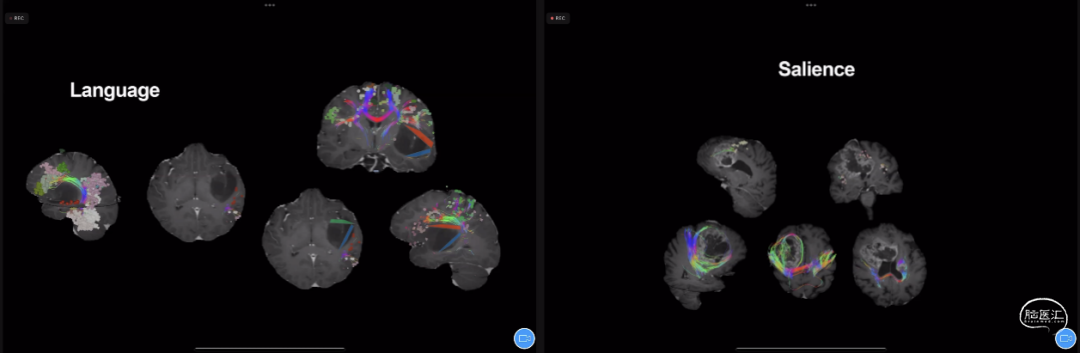

什么是神经网络,脑神经网络由7大主要网络系统构成,并衍生出17个小网络系统,它们分别是:CEN(Central Executive Network)——中央执行网络;Limbic——边缘系统网络;Vision——视觉网络;Sensorimotor——感觉运动网络;Salience——显着网络;DMN(Default Mode Network)——固定模式网络;DAN(Dorsal Attention Network)——背侧注意网络。

Michael Sughrue教授团队及世界其他团队通过各样的磁共振成像进行了许多研究,发表了许多成果,共同绘制了人脑网络连接组学的图谱。

基于人脑网络连接组学图谱,结合脑内病变位置,通过计算机辅助我们可以更加清楚明确各种病变与各种网络系统的解剖关系。